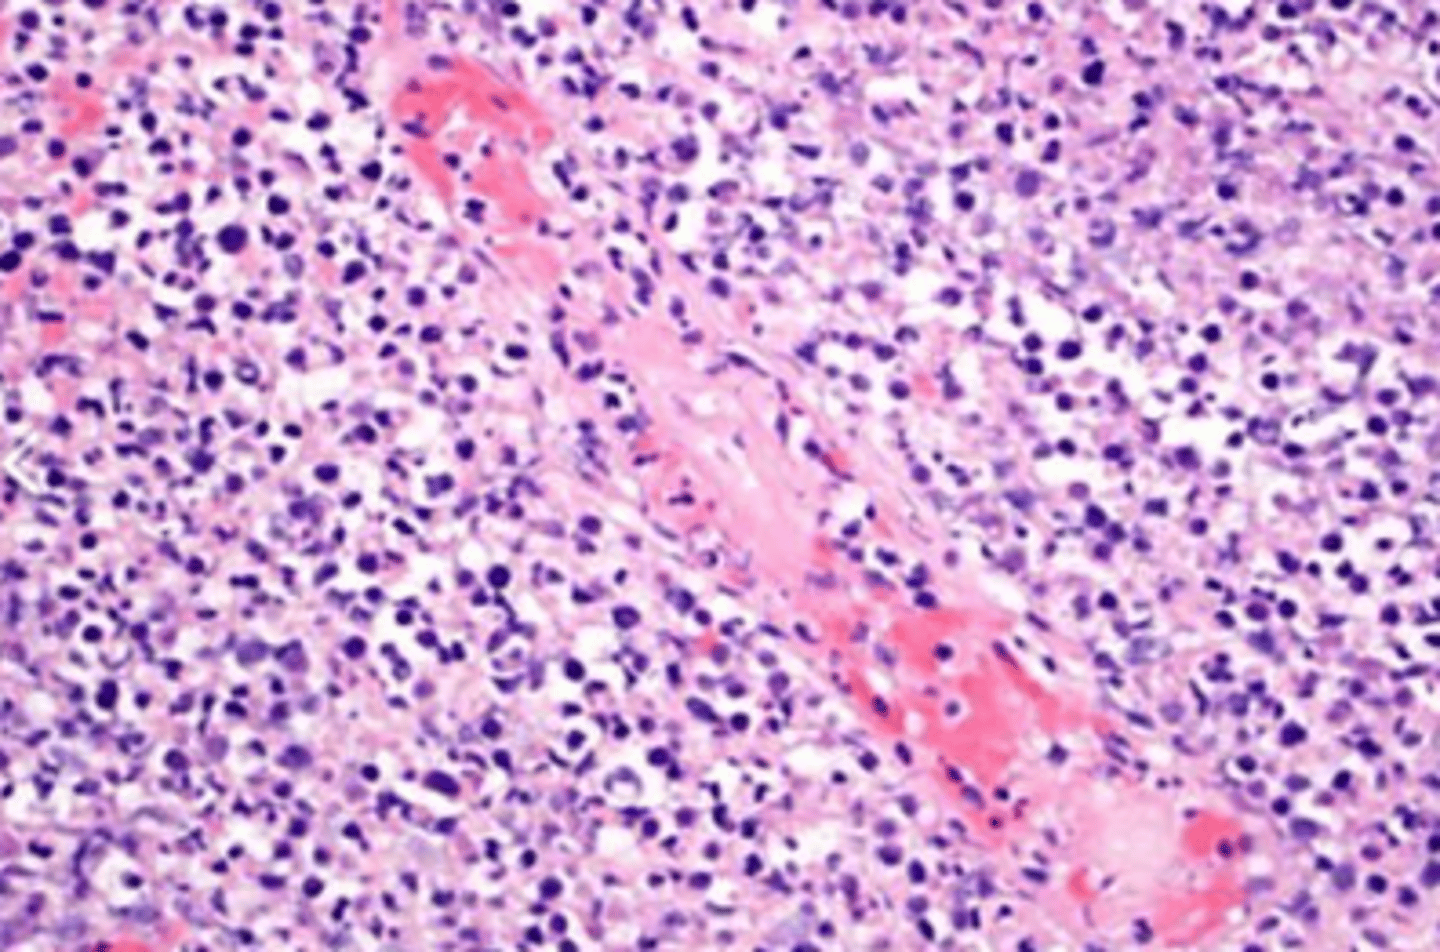

angioimmunoblastic T cell lymphoma

aggressive form of peripheral T-cell lymphoma in which proliferation of atypical lymphoid cells is combined with the formation of the arborizing high endothelial venules and a diffuse proliferation of follicular dendritic cells.